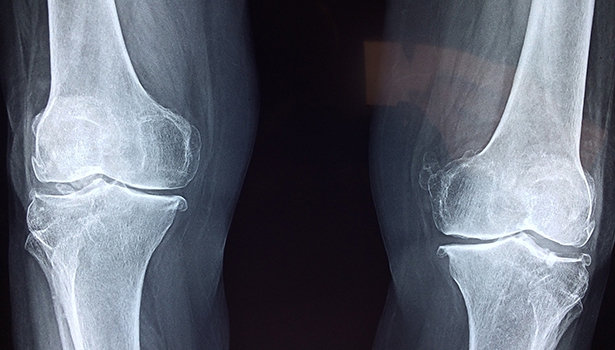

Vitamin D unterstützt in der Schwangerschaft die Gesundheit von Mutter und Kind, beim Fötus ist es vor allem für das Wachstum und die Entwicklung gesunder Knochen wichtig.

Ein Vitamin-D-Mangel wird mit mütterlichen und fetalen Kalziumstörungen, z. B. verminderte Kalziumspiegel, Fehlbildungen im Zahnschmelz sowie bei den Müttern mit gestörter Knochenmineralisierung (Osteomalazie) und Präeklampsie verbunden. Ein Vitamin-D-Mangel kann auch das Risiko für den Gestationsdiabetes erhöhen. Ein Review und die Meta-Analyse von 29 Studien zeigten eine U-förmige nichtlineare Beziehung zwischen Vitamin-D-Spiegeln (Serum) und dem Risiko für Gestationsdiabetes. Das geringste Risiko wurde bei Frauen mit einer guten Vitamin-D-Versorgung (40 bis 90 nmol/l) beobachtet, während Frauen mit niedrigen Spiegeln (< 20 ng/ml) ein um 26 % höheres Risiko für Gestationsdiabetes hatten. Ergänzungen von Vitamin D können das Risiko für den Gestationsdiabetes deutlich verringern. Die Mechanismen, über die ein Vitamin-D-Mangel das Risiko eines Gestationsdiabetes beeinflusst, sind nicht vollständig geklärt, vermutlich spielen dabei die Insulinresistenz und eine gestörte Glukosehomöostase eine Rolle. Bei einem nachgewiesenen Vitamin-D-Mangel in der Schwangerschaft wird empfohlen, die Ergänzung von 1.000 bis 2.000 I.E. Vitamin D einzuleiten.